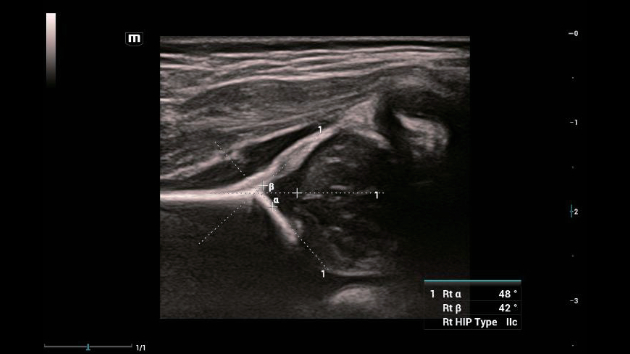

Soluzioni di diagnostica per immagini complete con tecnologia ZST+

La piattaforma ZST+ è un'innovazione straordinaria, che rappresenta un'evoluzione nel campo dell'ecografia. Grazie alla trasformazione delle metriche a ultrasuoni dal beamforming convenzionale all'elaborazione basata sui dati di canale, supera la tradizionale limitazione del trade-off tra risoluzione spaziale, risoluzione temporale e uniformità dei tessuti, offrendo una qualità d'immagine eccezionale per infinite soluzioni di imaging con miglioramenti continui.